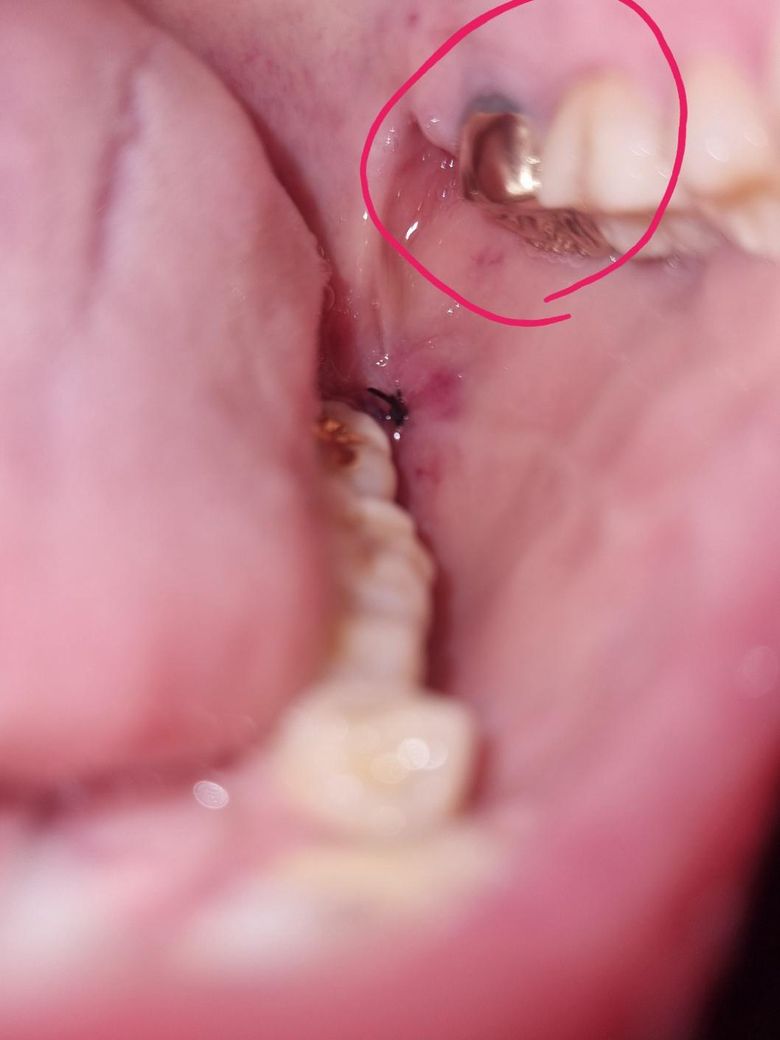

어제 오후에 왼쪽 윗,아래사랑니뽑고 그앞에있는 왼쪽 윗어금니(크라운) 윗부분이 약간회색? 이되었습니다. 저회색부위를 만졌다가 뭐잘못될까봐 일단 만지지는않았고 혀로 만졌을때 크라운이 흔들리지는않습니다. 통증x

• 3번 째 사진

1,2. 발치하면서 옆 치아를 건드려 크라운이 약간 벗겨진 것일 수도 있는데 만약 그랬다면 교합 안맞고 바로 알아차립니다

그보다는 애초에 크라운 변연이 짧아서 치아가 노출되어 있는 상태거나 아니면 잇몸퇴축으로 점차 드러난 것 같습니다

사진에 보이는건 치아 색이 변한게 아니라 나이가 들면서 잇몸이 내려가면서 치아가 노출되서 치아가 보이는겁니다. 단순 발치엿다면 3일정도 지나셧고 지혈도 됫고 통증도 없다면 운동을 하셔도 됩니다.

금리로 씌운 부위의 경계 부위는 착색 등으로 인해서 색이 어두워 보일 수 있습니다.